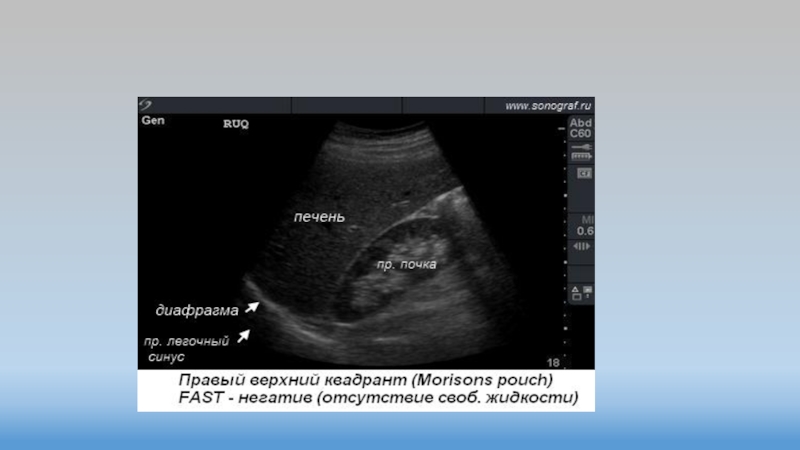

FAST ( Focused Assessment with Sonography for Trauma ) –

это

ограниченное ультразвуковое исследование, направленное исключительно на поиск свободной жидкости в

брюшной полости, в перикардиальной и плевральных полостях, а также определения пневмоторакса.

Исследование должно проводиться быстро (в течение 3 – 3.5 минут).

Слайд 14Точки 1-2

Точки 1-2

Слайд 15Точка 1

Точка 1